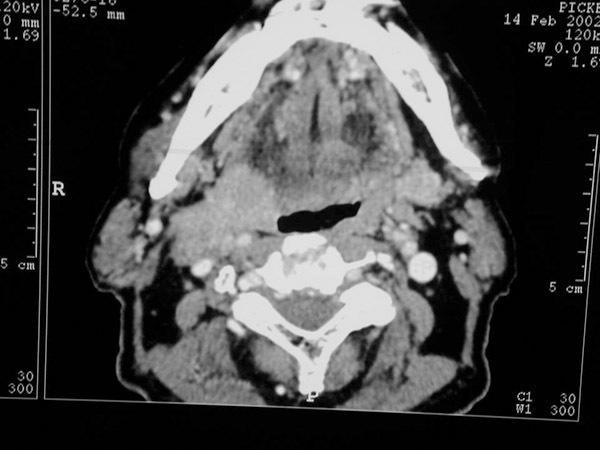

Tumeur de la paroi latérale droite de l’oropharynx

Coupe scanner axiale montrant une tumeur de la paroi latérale droite de l’oropharynx.